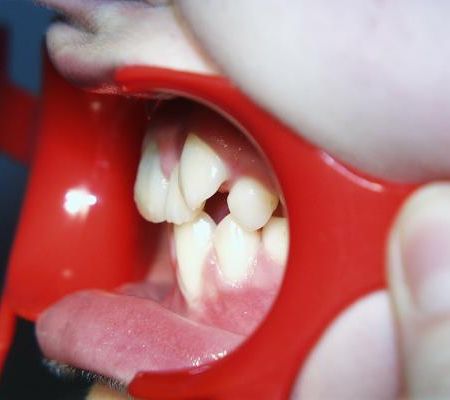

Mundfotos im Vergleich

Vor und nach der Zahnverbreiterung

Die seitlichen Schneidezähne wurden nach Beendigung der aktiven Behandlung vom Hauszahnarzt mit laborgefertigten Keramik-Verblendschalen, sog. Veneers, verbreitert, die Eckzähne mit plastischem zahnfarbenem Füllungsmaterial und Beschleifen zu Schneidezähnen umgestaltet. Bei den im Unterkiefer ausgleichend entfernten beiden Zähnen handelte es sich um Milchbackenzähne, die keine bleibenden Nachfolger hatten. Auch diese Lücken wurden allmählich geschlossen, so daß die Seitenzahnreihen anschließend gut aufeinander paßten.